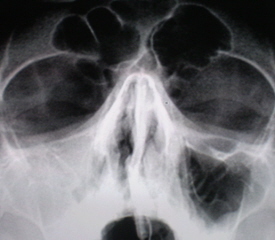

На снимках регистрируется окаймляющая стенки пазухи плотная тень шириной от 0,3 до 0,5 см и более, которая отлича­eтcя от таковой при остром процессе не только шириной, но и стойкостью. При динамическом наблюдении эта тень не исчезает – иллюстрации 8 и 9.

На иллюстрации 8. Определяется снижение прозрачности лобной пазухи довольно однородной структуры с локальным утолщением её над правой орбитой. Справа определяется пристеночное снижение прозрачности гайморовой полости с не четким и неровным контуром, особенно базально. Слева определяется субтотальное снижение прозрачности, с выраженным пристеночным снижение прозрачности вдоль верхней стенки.